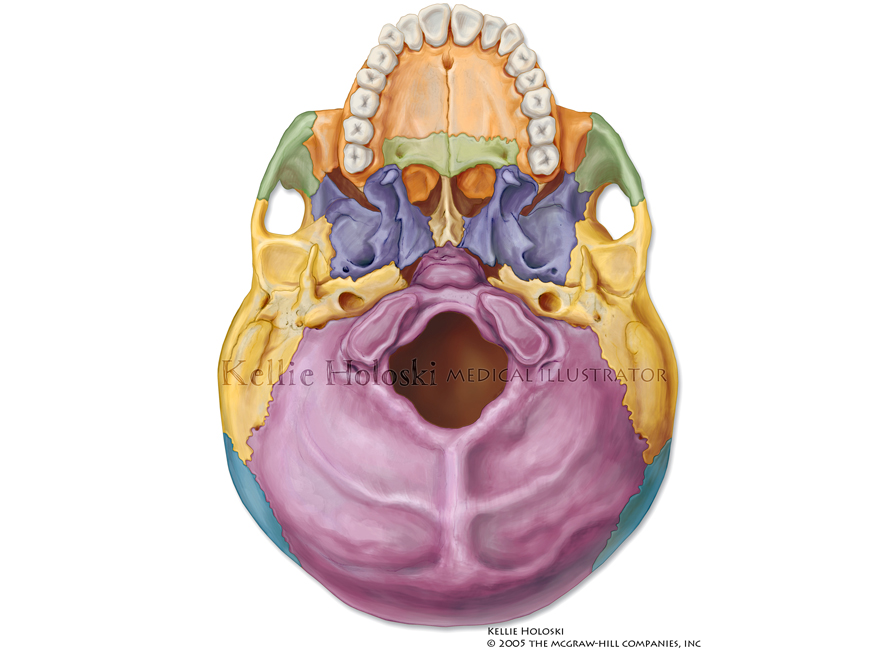

Base of Skull: Exterior,

Adobe Photoshop

Published in Human Anatomy, 1st Edition by Michael McKinley, Valerie O’Loughlin;

©The McGraw-Hill Companies -